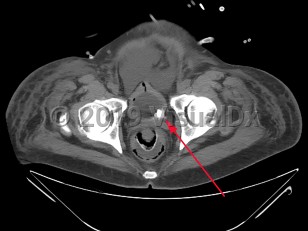

Urinary bladder calculus

The decreased incidence of bladder calculi is largely because the 2 conditions principally associated with bladder stones, urinary stasis (most commonly due to benign prostatic hyperplasia [BPH]) and urinary tract infections (UTIs), are now more easily and frequently treated. BPH, once only effectively treated with surgery, is now frequently effectively and more easily treated with a combination of alpha blockers, 5-alpha reductase inhibitors, or transurethral resection. Consequently, the number of men suffering from chronic urinary retention has significantly decreased. Urinary stasis in the setting of neurogenic bladder is also a common etiology of bladder stone formation.

When urine is chronically retained in the bladder, any nidus, such as a small fragment of a stone passed from the ureter, a bladder diverticulum, or a foreign body such as a ureteral stent or Foley catheter, can serve as a site for the precipitation and deposition of uric acid. In most retrospective studies of bladder stone composition, nearly all stones (as many as 80%) are entirely composed of uric acid, and most of the remainder contain a substantial portion of uric acid. Interestingly, neither gout or hyperuricemia appear to be contributory factors in the formation of bladder calculi. This is qualitatively different than nephrolithiasis, which in the United States is primarily due to calcium oxalate or calcium phosphate stones.

Bladder stones, particularly large and nonobstructive stones, do not frequently cause symptoms. Larger stones are thought to be less able to move significantly within the bladder and cause injury to the bladder wall and seem to be less prone to lodge in the bladder infundibulum / neck and cause acute obstruction. When patients do present with symptoms, they may be nonspecific and include suprapubic discomfort, hematuria, dysuria, urinary frequency, urinary hesitancy or poor urine stream, penile pain in male patients, or cloudy urine.